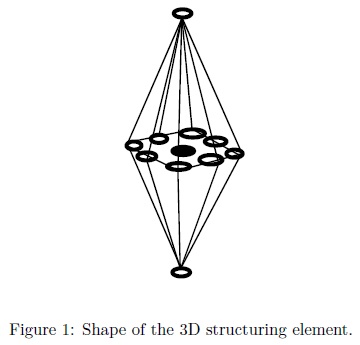

In MM, the basic transformations are the erosion εμB(f) and dilation δμB(f) [16], where B represents the 3D structuring element which contains its origin in the center. Figure 1 illustrates the shape of the structuring element used in this paper.  denotes the transposed set of B respect its origin,